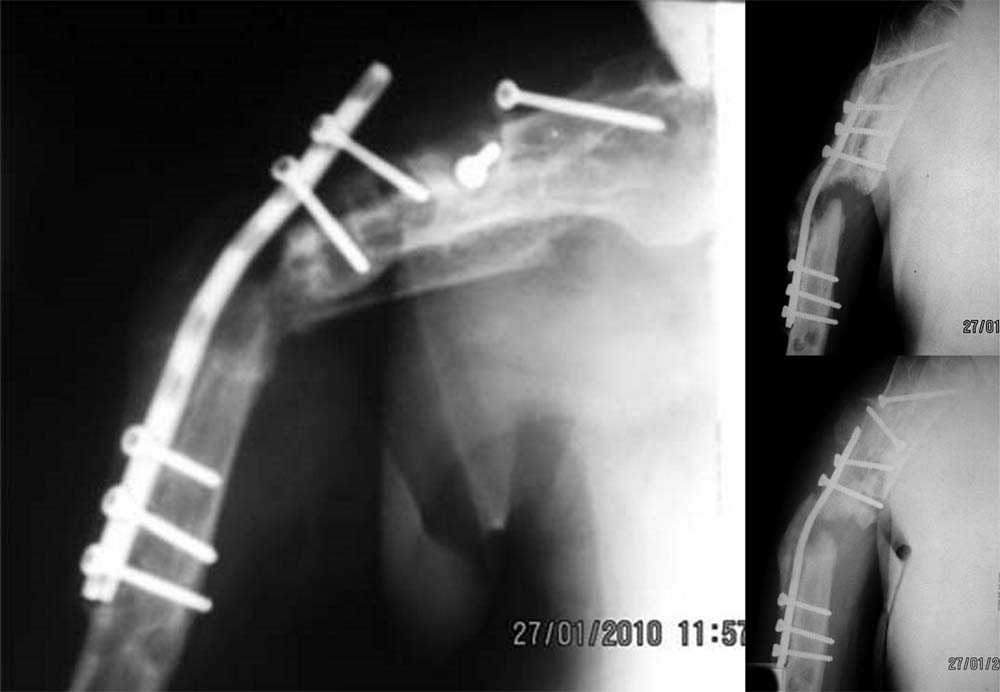

был ли остеосинтез с диастазом - неизвестно, но неадекватность фиксации пластиной достаточно очевидна.

1 пластина тонкая

2 всего 6 шурупов через пластину - для плеча это минимальное требование при свежем переломе

3 проксимальный фрагмент на момент ( или в ходе) второй операции был расколот , о чем свидетельствует наиболее проксимальный lag screw, то есть прокс 3 шурупа через пластину были введены в расколотый фрагмент. Неудивительно, что пластину вырвало

Здравствуйте Владимир! На всех рентгенограммах определяется лизис костной ткани вокруг шурупов, на боковой проекции похоже секвестр, это -- в пользу остеомиелита. Рекомендую: удаление металлоконструкций краевую резекцию концов плечевой кости, ревизию каналов после удаленных шурупов, при наличии признаков остеомиелитических грануляций провести кюретаж. Наложить спице-стержневой АВФ + открытую репозицию отломков. При необходимости проточно- промывное дренирование. Желательно применение Коллапана интраоперационно.